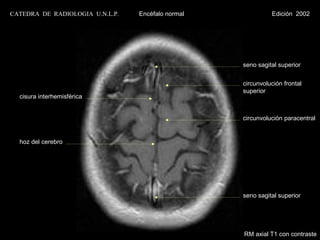

seno sagital superior

circunvolución frontal

superior

cisura interhemisférica

circunvolución paracentral

hoz del cerebro

RM axial T1 con contraste